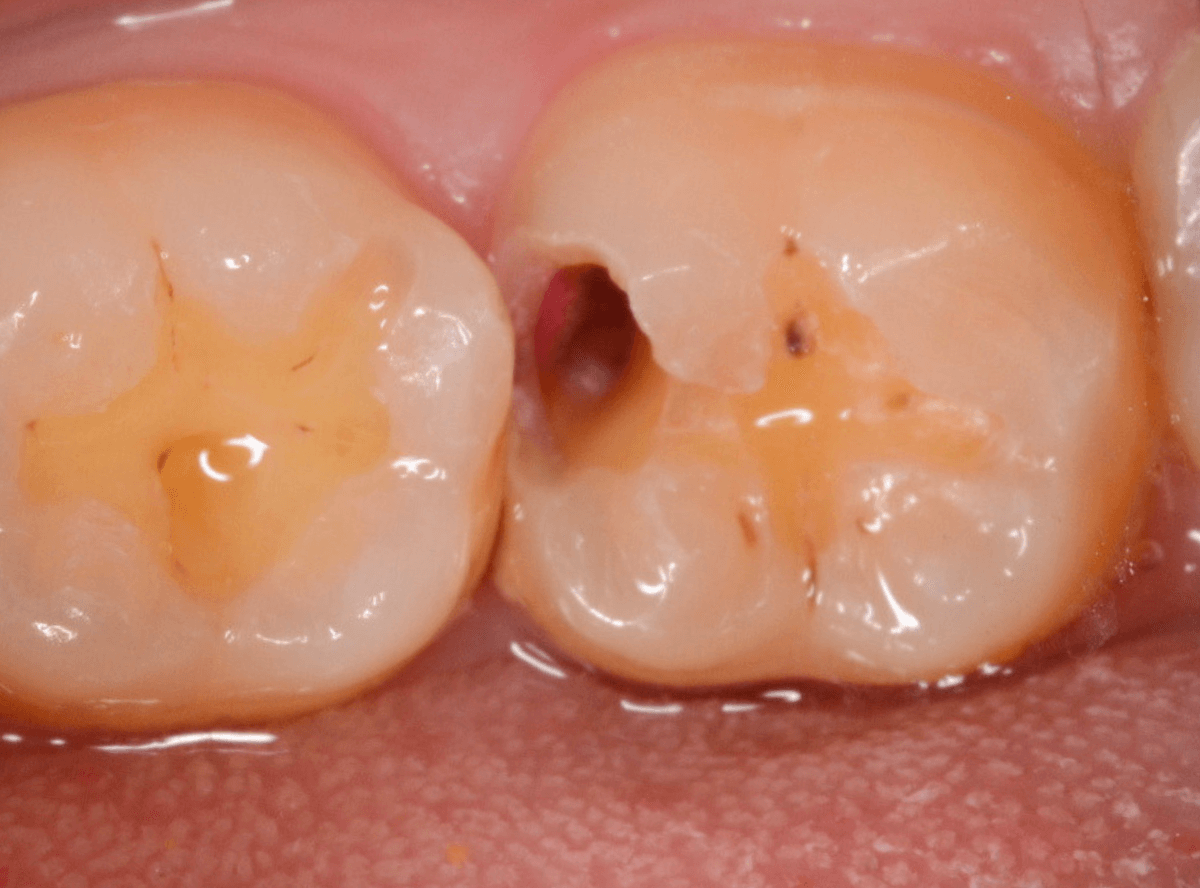

Case.8 大きな虫歯なのに、レントゲンではっきり写らない

こちらも定期検診希望で来院された患者さんです。

お口の中を拝見すると、明らかに虫歯がありました。

3本虫歯になっており、特に中央の小臼歯はかなり大きな虫歯になっているのが予想されます。

治療前にレントゲン写真で虫歯の大きさを確認するつもりが・・・あまりはっきり写ってきません。

患者さんに状況を説明して、歯を少しずつ削りながら虫歯を確認する事になりました。

まず、一番大きな虫歯と思われる部分を小さく削って確認します。

予想通り、虫歯が見えてきました。

隣りの奥歯と一緒に虫歯の治療を進めます。

色が染まっているところがまだ虫歯が残っている部分です。

2本とも、虫歯を全て取り切りました。

特に手前の歯はかなり広めの虫歯になっていました。

最終的に、手前の虫歯の除去も終わったところです。

手前の歯の虫歯は中央の歯まで達していました。

このように明らかに大きな虫歯があると診断されるような状況でも、レントゲン写真でうまく診断できない場合もあります。